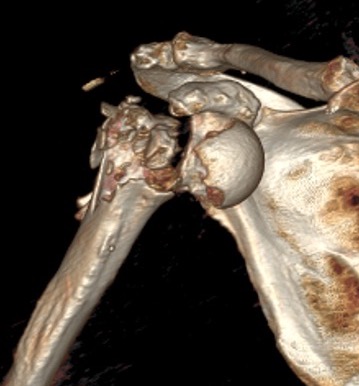

Four part